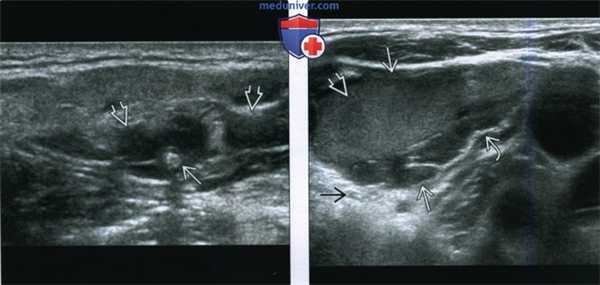

(Слева) Нa поперечной сонограмме верхних отделов шеи визуализируется кистозное объемное образование смешанной структуры с расширенными синусоидами и эхогенным флеболитом, наличие которого позволяет сделать вывод о венозной мальформации. Тем не менее, УЗИ не позволяет оценить распространенность больших мальформаций в глубокие отделы шеи или подтвердить множественность (из статьи на сайте «Лучевая диагностика: УЗИ»).

(Справа) На поперечной сонограмме у ребенка с безболезненным объемным образованием в нижних отделах шеи визуализируется кистозный очаг с ровными краями: расширенное синусоидальное пространство с небольшими включениями дебриса и перегородками внутри. Обратите внимание на заднее акустическое усиление - признак кистозной природы образования.